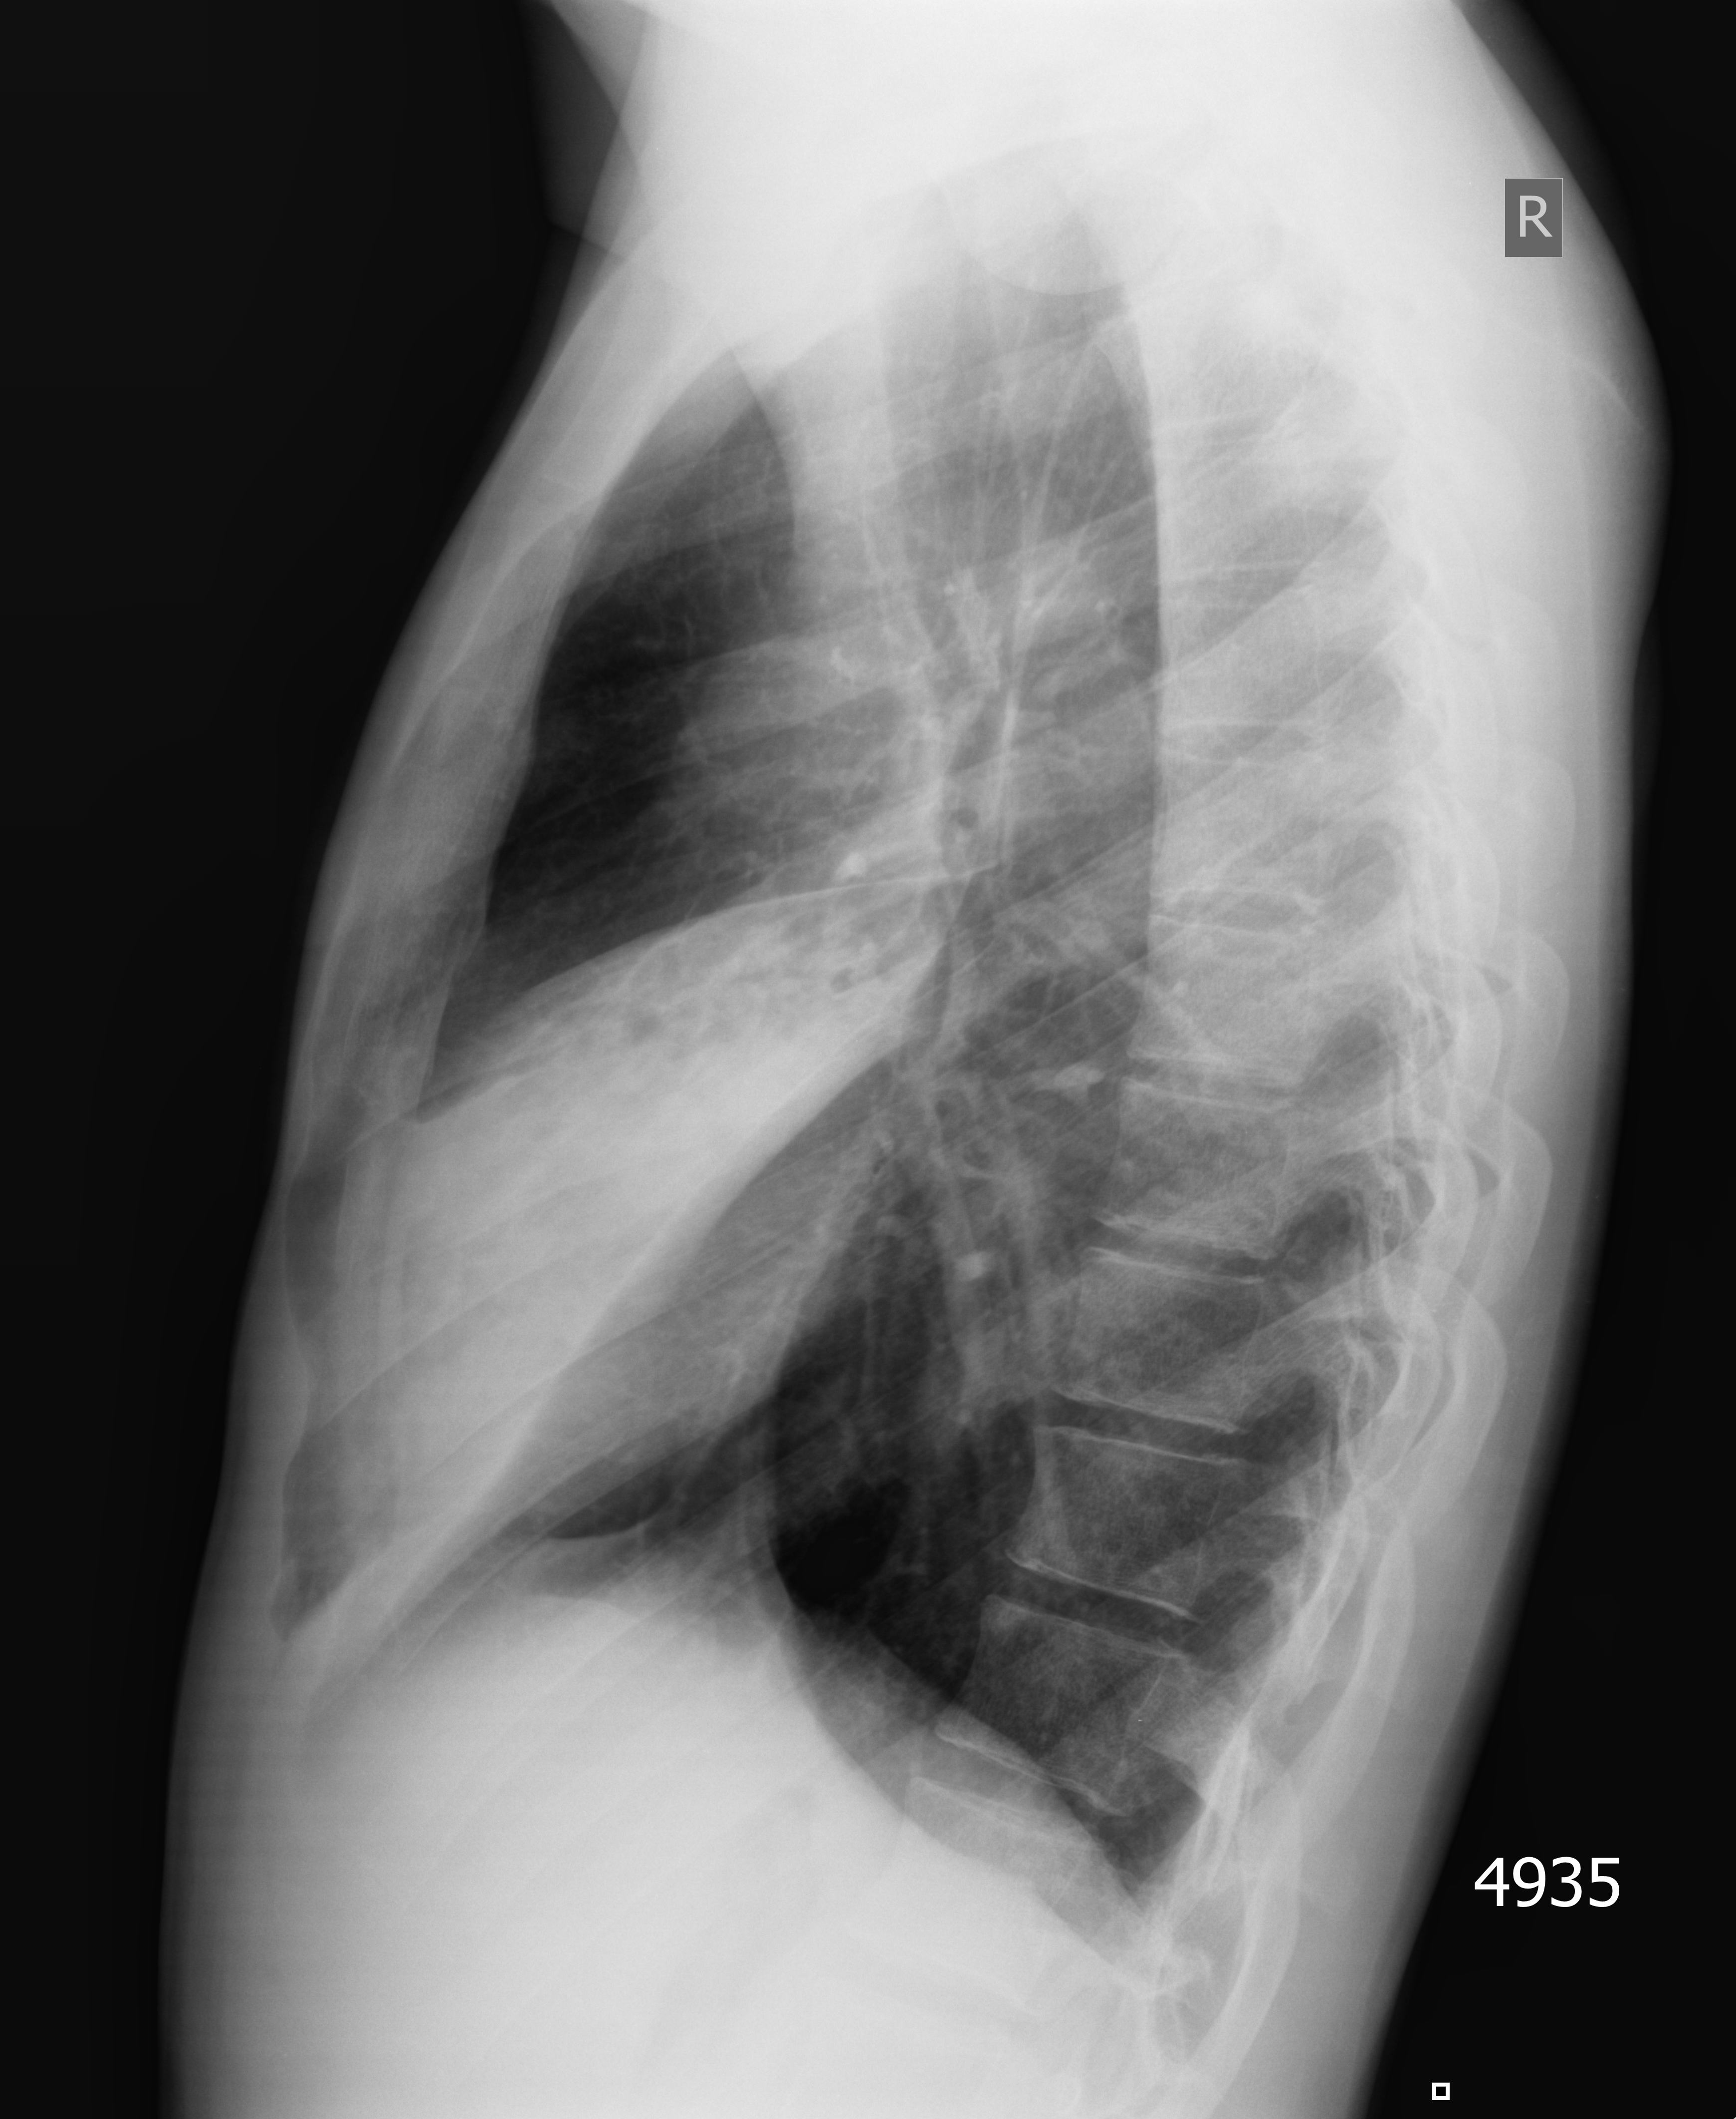

Правостороння пневмония, УЗИ и рентген

Молодой парень. Высокая температура, сухой кашель.

Датчик по правой средней линии спереди смещается с грудной клетки в брюшную полость.